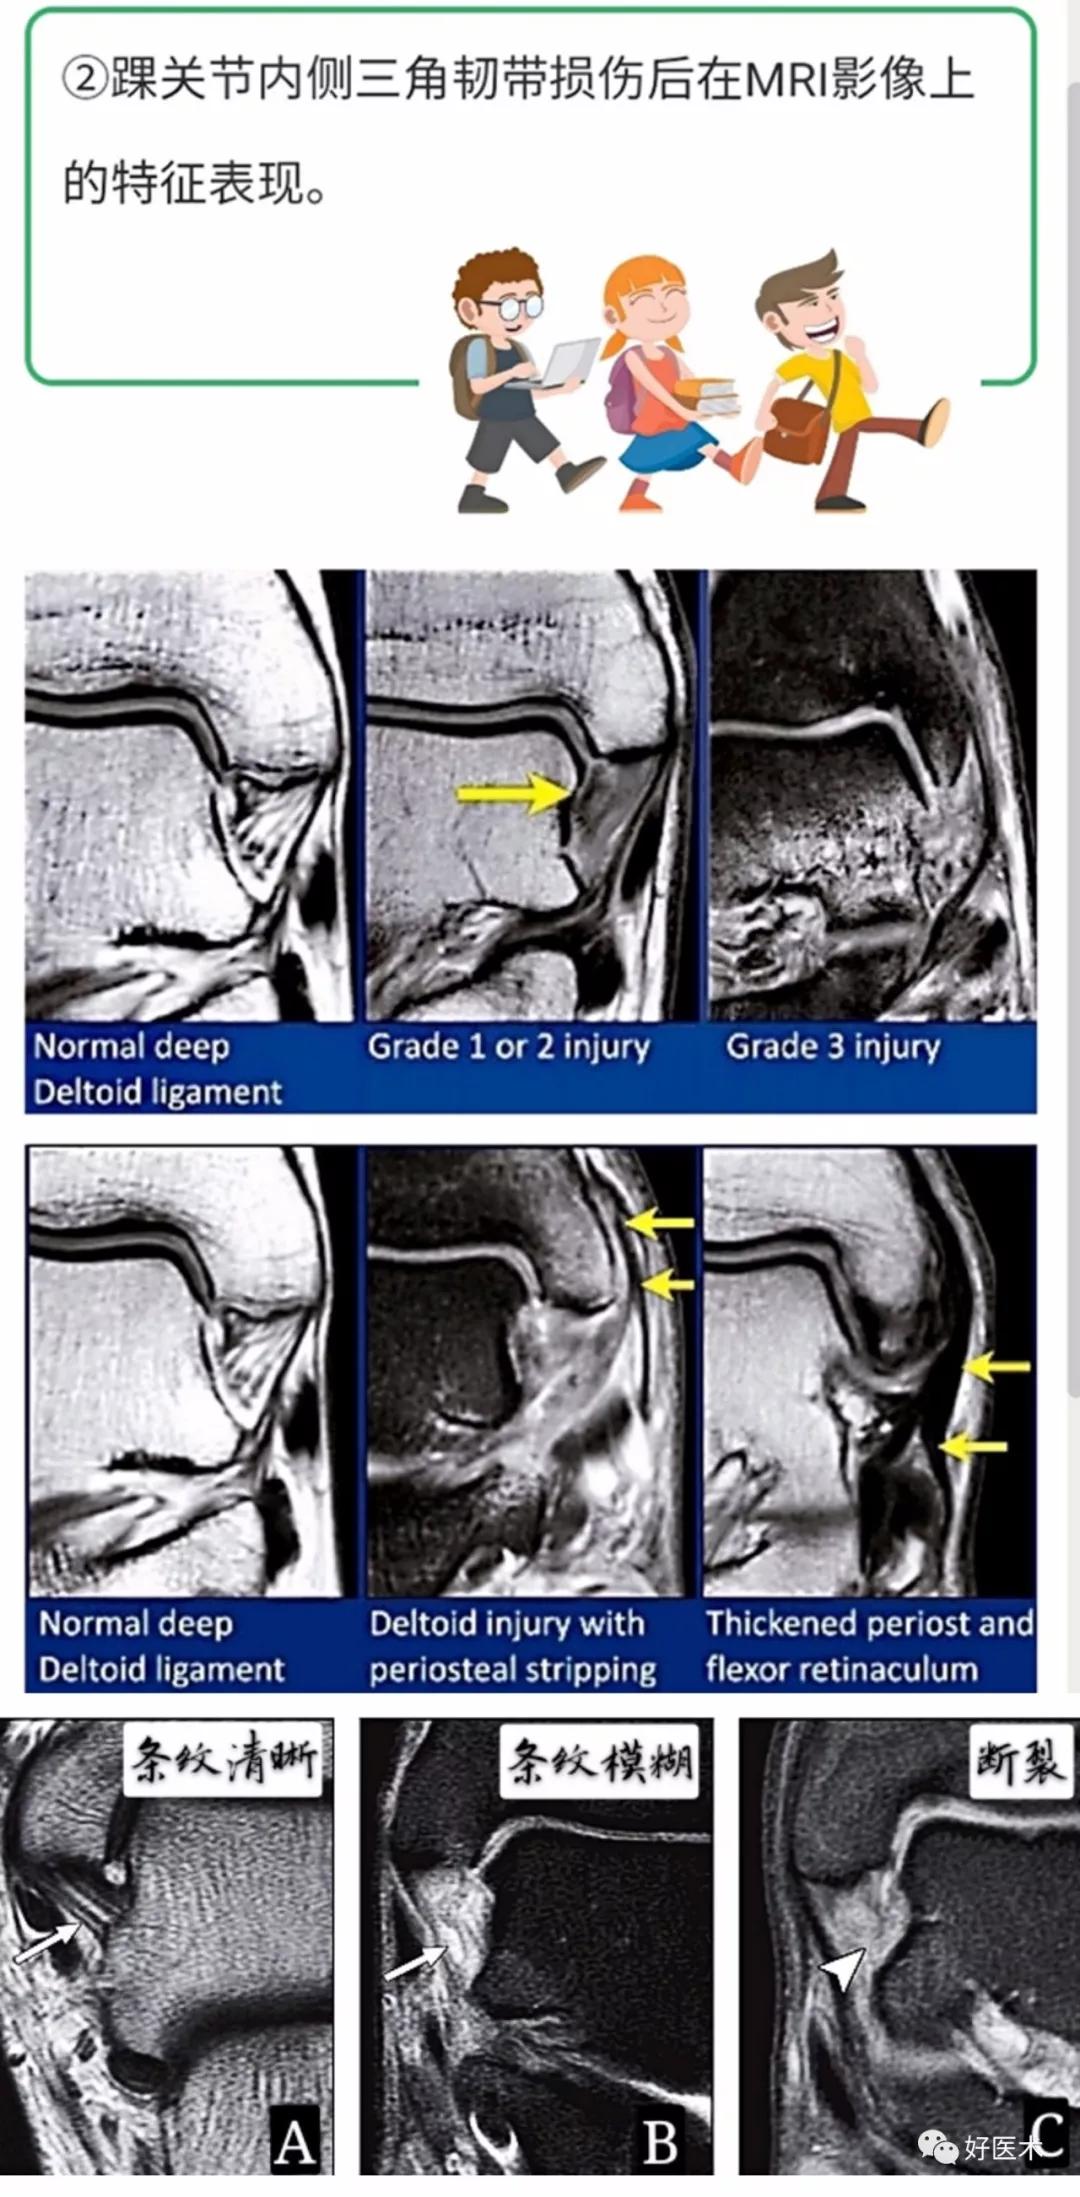

三、踝关节周围韧带异常的MRI特征